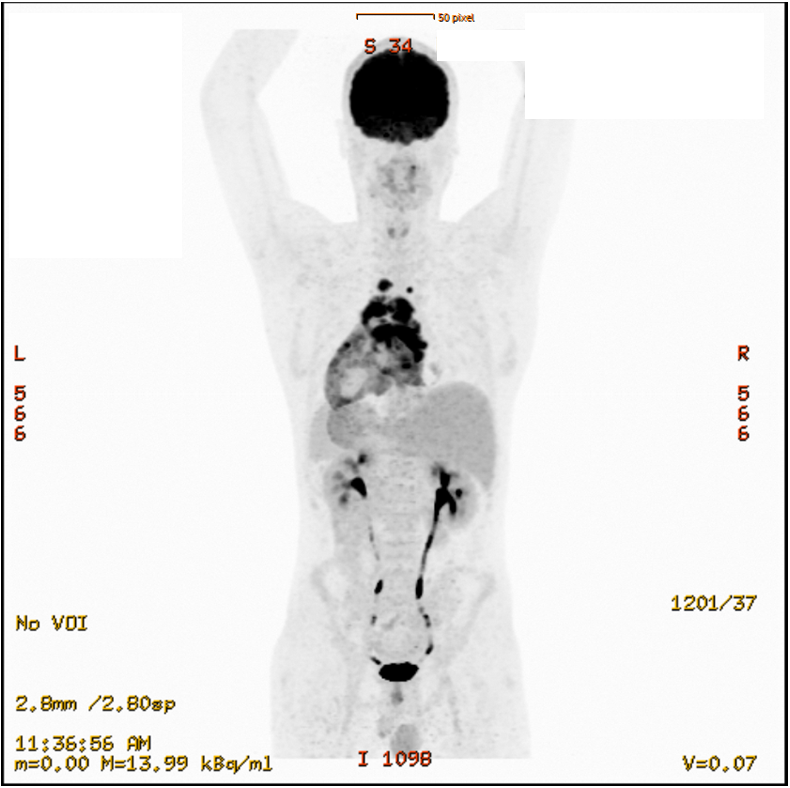

Case Presentation: A 22-year-old previously healthy male presented with cardiogenic shock and echocardiographically confirmed pericardial tamponade (Figure 1). Emergency pericardiocentesis drained 2.5 L of hemorrhagic fluid, and the patient was stabilized in the ICU with inotropic support. Transthoracic echocardiography revealed global left ventricular dysfunction (EF ~10%). Empiric antibiotic therapy was initiated. Cardiac MRI showed diffuse myocardial edema consistent with perimyocarditis, along with a large pericardial effusion. Endomyocardial biopsy revealed lymphocytic infiltration without eosinophils or giant cells. High-dose corticosteroids and chochizin were administered, leading to full recovery of left ventricular function. Extensive infectious workup remained negative. However, repeat cardiac MRI revealed a contrast-enhancing mediastinal mass with infiltrative growth into the right atrium and ascending aorta as well as relapse pericardial efusion. PET-CT demonstrated intense FDG uptake in the lesion, raising suspicion for malignancy (Figure 2).Subsequent targeted CT guided biopsy confirmed the diagnosis of a high-grade, undifferentiated angiosarcoma originating in the mediastinum with direct cardiac invasion. The patient was transferred to an oncology center for further management and systemic therapy planning.

Figure 2: Fused PET/CT image demonstrating increased metabolic activity in pericardial and mediastinal structures surrounding the heart